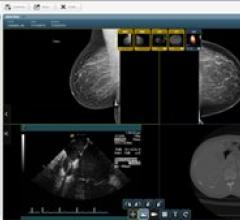

Despite decades of progress in breast imaging, one challenge continues to test even the most skilled radiologists ...

Two-dimensional plus 3-D breast imaging increases cancer detection rates by 11 percent, and could be particularly useful in detecting cancer in women with dense breasts, a new study suggests.

Magnetic resonance imaging (MRI) has emerged as a valuable imaging modality for breast cancer detection and staging. Dynamic contrast-enhanced MRI (DCE-MRI) is the most sensitive technique for screening high-risk women and for evaluating the extent of disease in patients with a recent diagnosis of breast cancer.[1,2] Despite its numerous advantages, the moderate specificity of DCE-MRI can result in a substantial number of false positive findings that translate to high recall rates and unnecessary biopsies.

In the small rural town of Kingman, AZ — approximately 90 minutes southeast of Las Vegas — most of its 28,000-plus population are economically disadvantaged; some of them still work in local gold and silver mines. So for women living in the area, getting a mammogram every year isn’t a priority; in fact, notes Dr. Christopher Johansen, Kingman Regional Medical Center (KRMC) Radiologist and Director of its Breast Imaging Program, “Many of our residents don’t have health insurance. And many aren’t even aware of the importance of getting annual mammograms.”